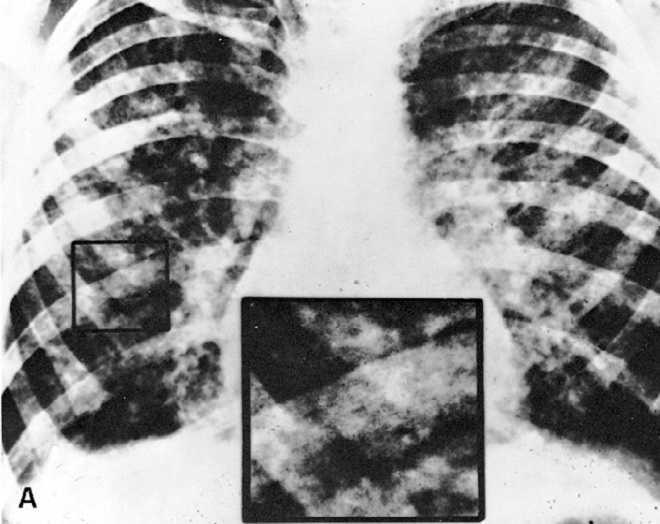

Затем паразит попадает в правый желудочек и предсердие по нижней полой вене. Через некоторое время из-за движения крови в сердце личинка выталкивается в легочную артерию и по ней переносится в легкие, где может прожить примерно в течение 10 дней. В отличие от зрелых особей, для которых воздействие кислорода губительно, личинки нуждаются в нем для полноценного развития.

Разъедая ткань легкого с помощью специального фермента из класса гиалуронидаз, гельминт внедряется внутрь альвеолы. Активно питаясь и увеличиваясь в размерах до 2-3 мм, аскарида проходит 2 стадии линьки.

Через 10 дней личинка начинает движение к гортани. Реснички мерцательного эпителия, покрывающие стенки бронхов и трахеи, проталкивают паразита вверх. В это время червь раздражает дыхательные пути. Человека мучает неприятный зуд. Возникающий в это время кашлевой рефлекс выталкивает аскариду в глотку или ротовую полость. Происходит повторное заглатывание паразита со слюной или мокротой. Гельминт вновь оказывается в кишечнике. Миграционная стадия при аскаридозе продолжается примерно 14-15 суток.